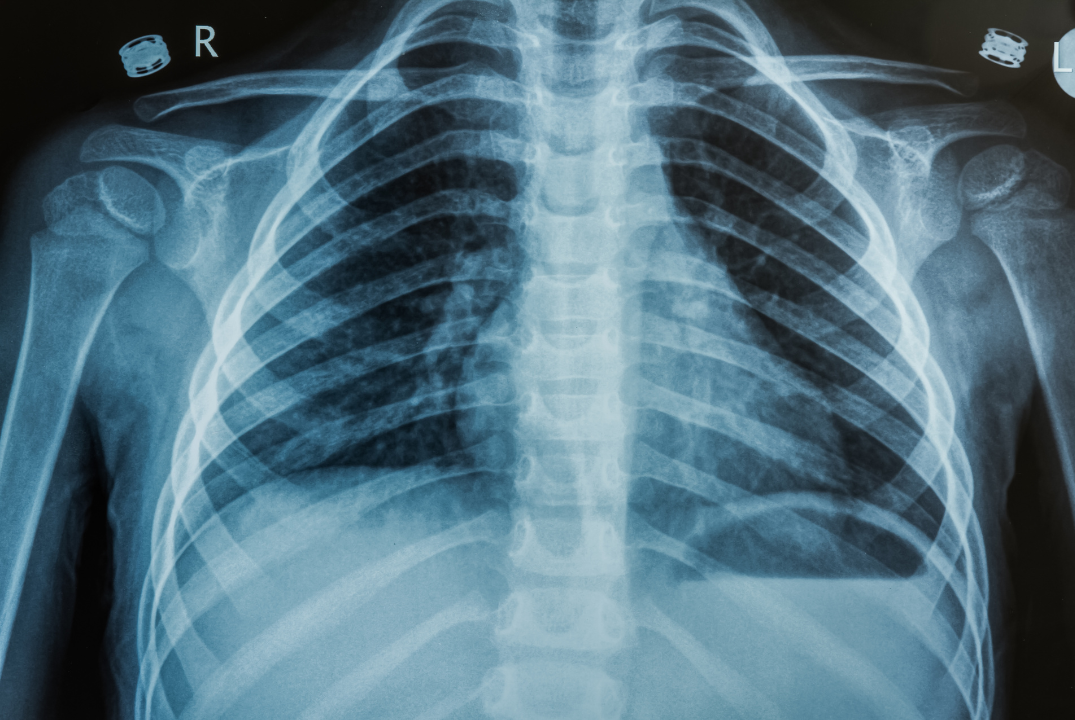

Lo que parecía una infección menor terminó revelando un hallazgo médico insólito: tenía un cuchillo completo alojado en su pecho, desde una agresión ocurrida ¡ocho años atrás!

Según el reporte publicado en el Journal of Surgical Case Reports, el paciente había sido apuñalado en 2016, pero tras recibir atención médica inicial, nunca se le realizó una radiografía torácica. Con el tiempo, olvidó el incidente y jamás presentó síntomas graves. Su cuerpo, en un acto de defensa biológica, encapsuló el cuchillo en una cápsula fibrosa, aislándolo de órganos vitales como el corazón y los pulmones.

Los médicos del Hospital Nacional Muhimbili realizaron una tomografía que reveló la silueta completa del cuchillo. En la cirugía, extrajeron el arma rodeada de tejido muerto y material purulento.